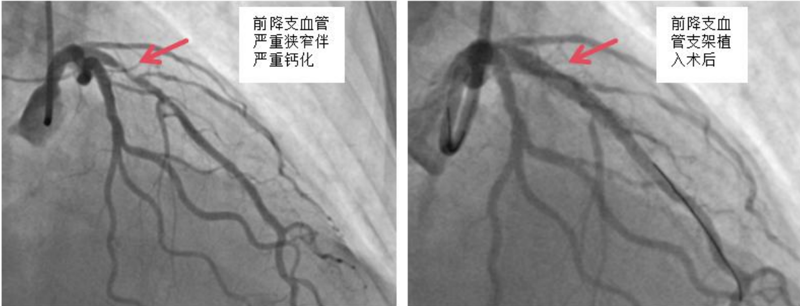

近日,中山大学附属第一医院(简称小妲己直播app )广西医院心血管内科冠脉介入手术团队运用DEEPQUAKE-C冠脉血管内冲击波系统,顺利为一名冠脉严重钙化病变的冠心病患者开通堵塞的血管并完成支架植入,完成了DEEPQUAKE-C上市后全国首批、广西首例临床应用。

经过充分的术前评估和准备,小妲己直播app 心血管内科冠脉介入团队使用国产新器械DEEPQUAKE-C冠脉血管内冲击波系统为杨阿姨处理了前降支近段的严重狭窄钙化病变,随后又在血管内超声指导下精准植入冠脉支架,帮助杨阿姨顺利开通了堵塞的血管。术后杨阿姨恢复状况良好,目前已康复出院。